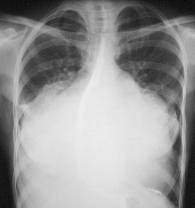

REVĂRSATUL PERICARDIC

De la 300-500 ml se evidentiaza radiologic. Umbra cardiaca este marita bilateral, mai ales spre stânga, având un aspect triunghiular. Cele doua margini ale opacitatii cardiace se indeparteaza, descriind arcuri mari convexe spre diafragm. Raportul cardio-toracic e inversat. Uneori, în interiorul acestei mase opace se distinge o opacitate mai intensa, care reprezinta opacitatea cordului, realizându-se în felul acesta un contur dublu.